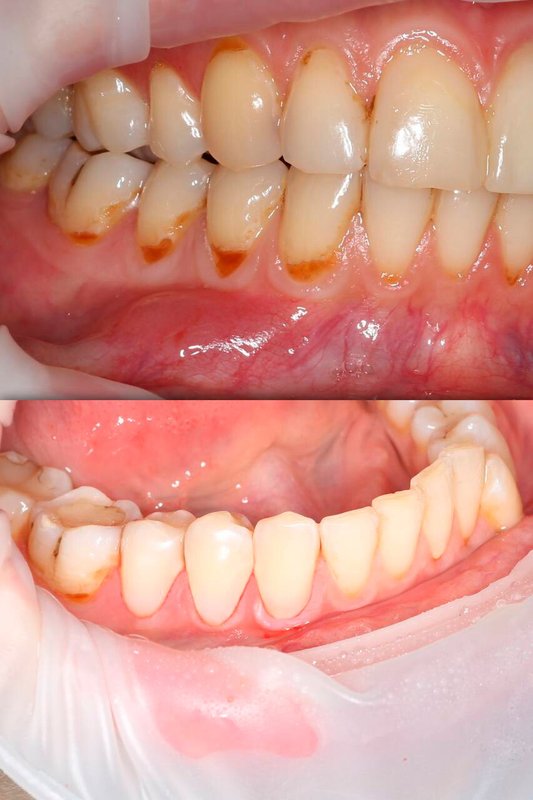

Фотогалерея